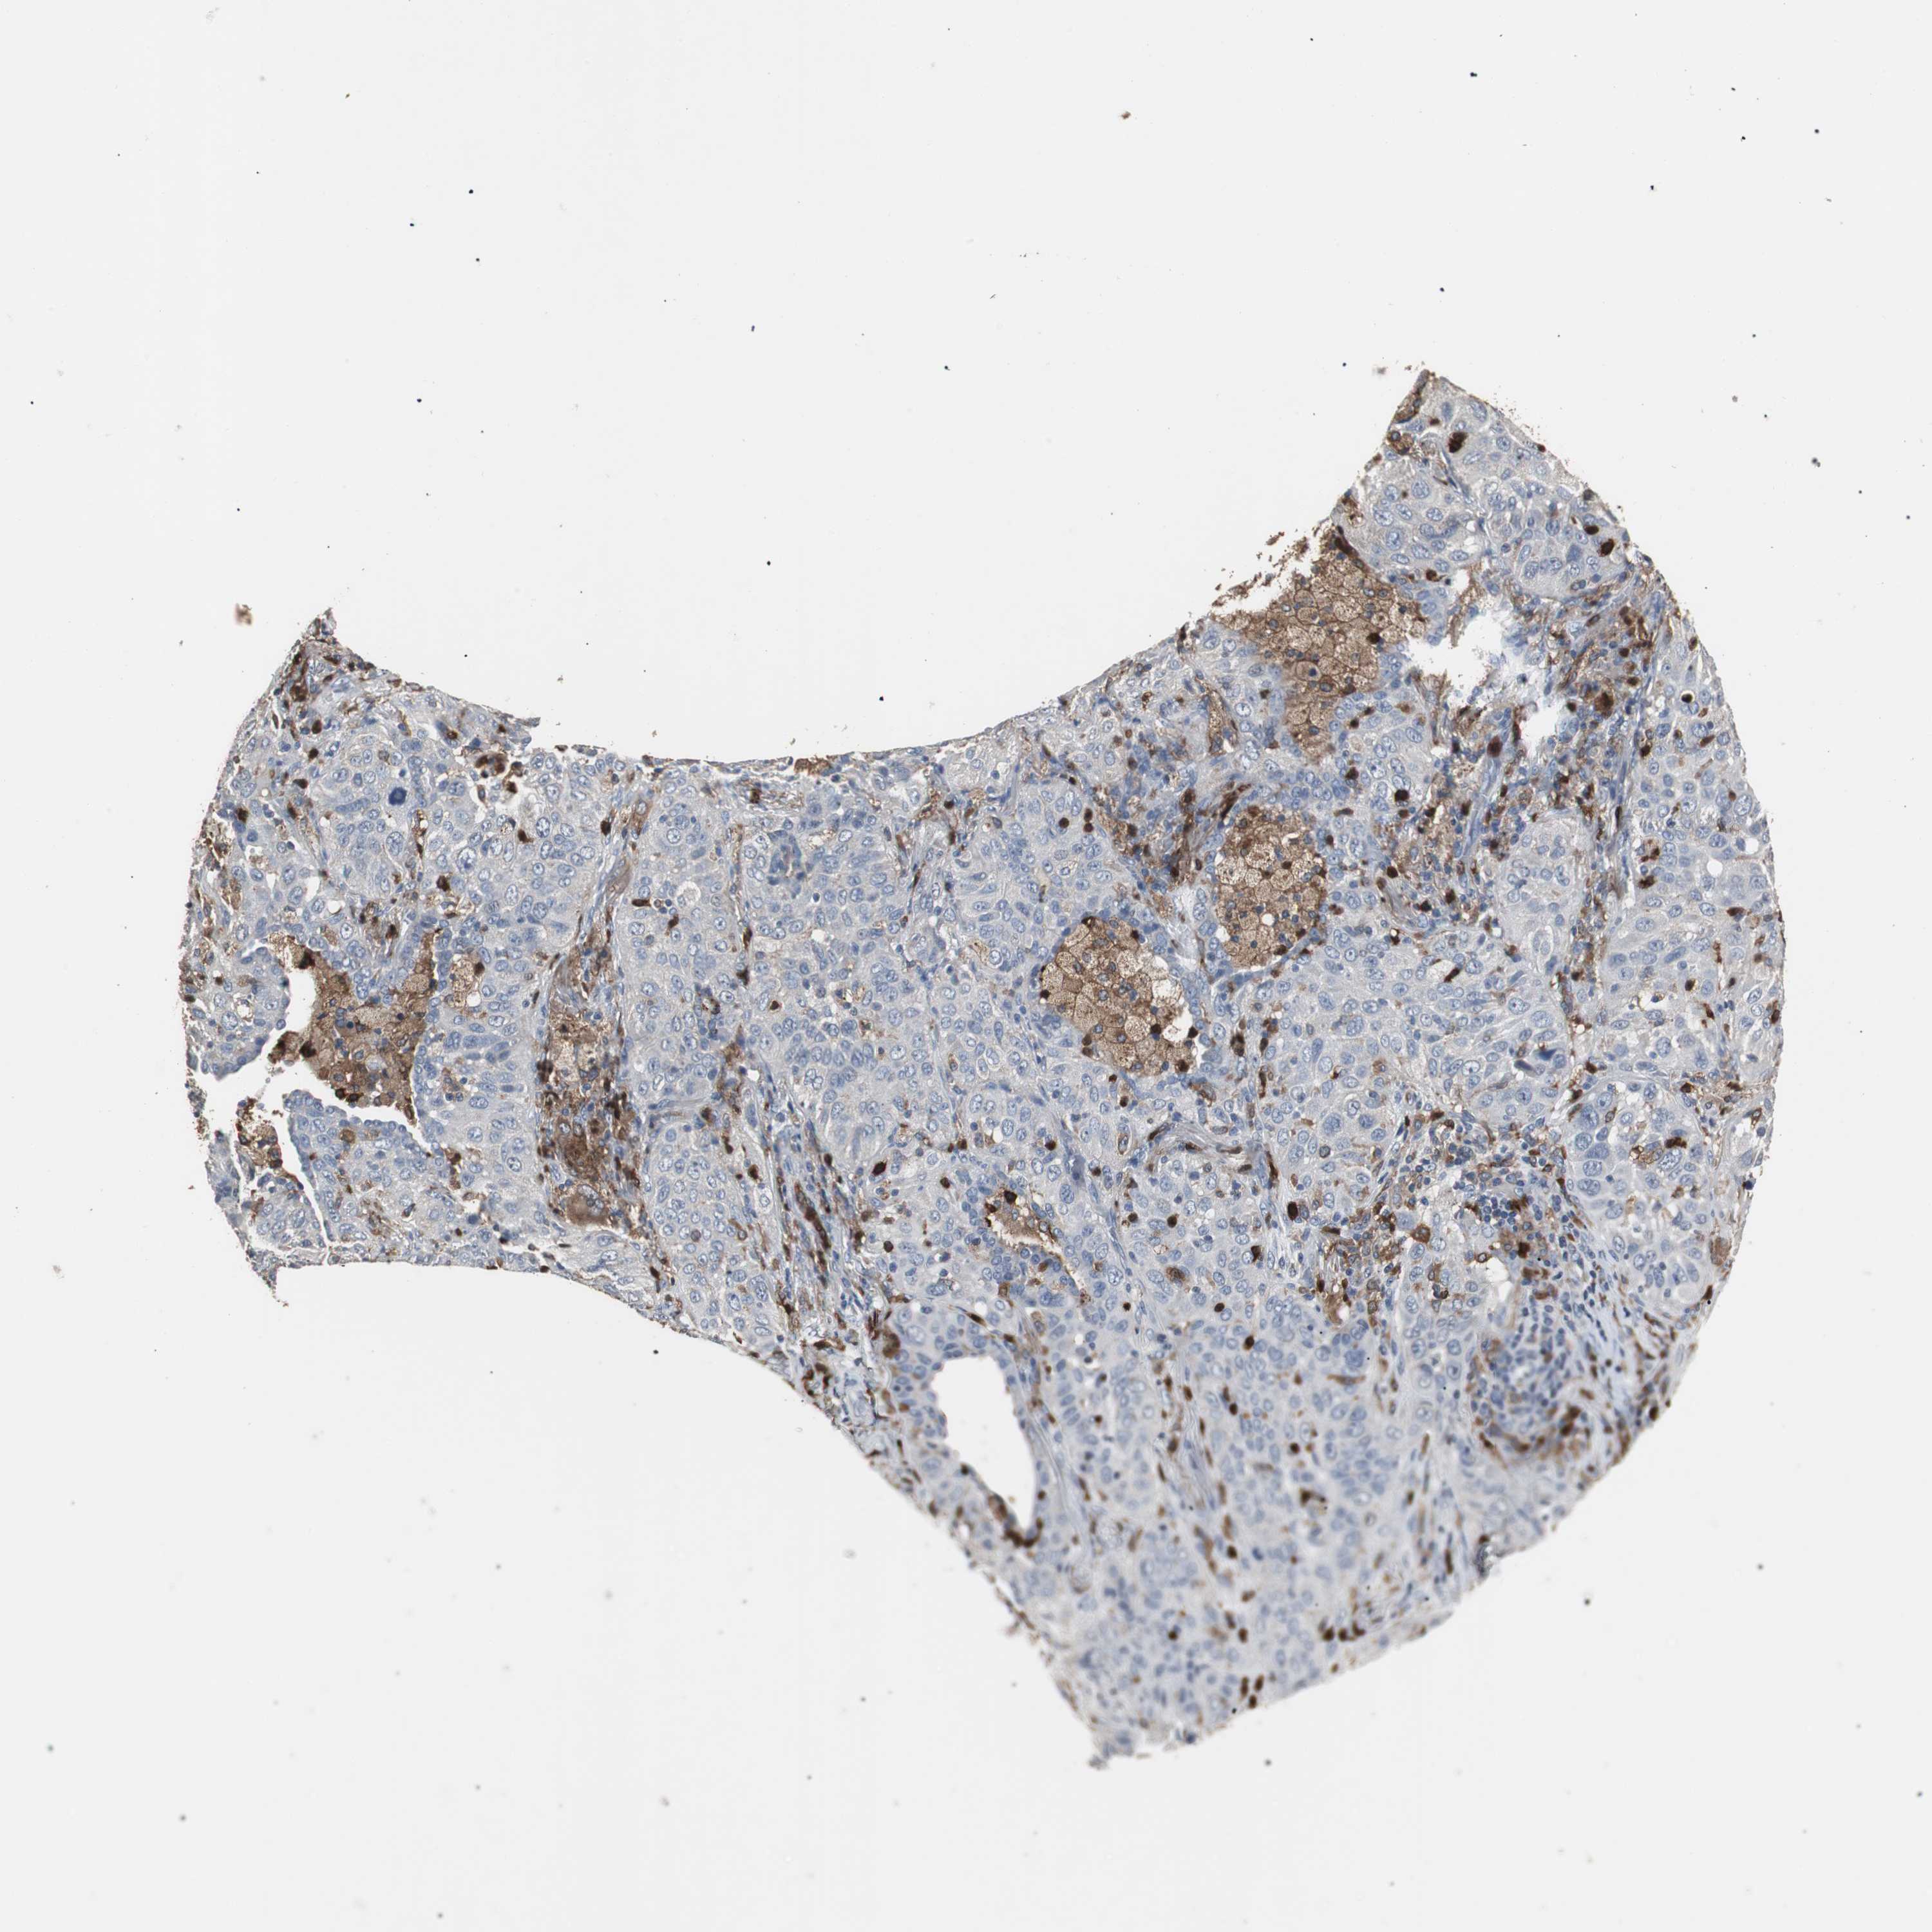

NCF2 is not prognostic in Lung Adenocarcinoma (TCGA)

: 33.55

Average pTPM 31.9

Number of samples 497